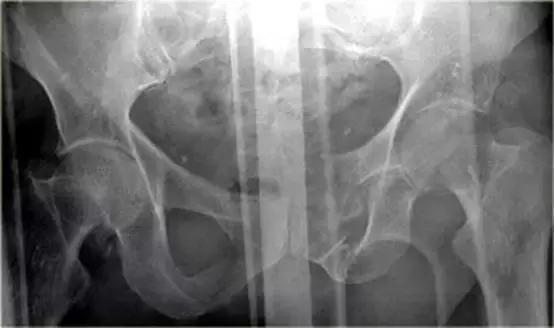

骨盆X线示耻骨骨折,膀胱区见游离骨片。

对骨盆外伤骨折病人应如检查?

该类病人存在盆腔动脉损伤及血肿形成,以及直肠、阴道、膀胱损伤的危险。

因此在常规CT(增强)检查之后需要加做膀胱造影 CT检查。

有一个指向膀胱的骨盆骨折碎片。

膀胱直肠隐窝积液。

10%骨盆骨折伴有膀胱破裂。

最初认为膀胱破裂都是由骨盆骨折引起,但现在知道只有1/3的膀胱破裂是因为游离碎骨片造成的,另外2/3是由于剪切伤作用于膀胱造成破裂。